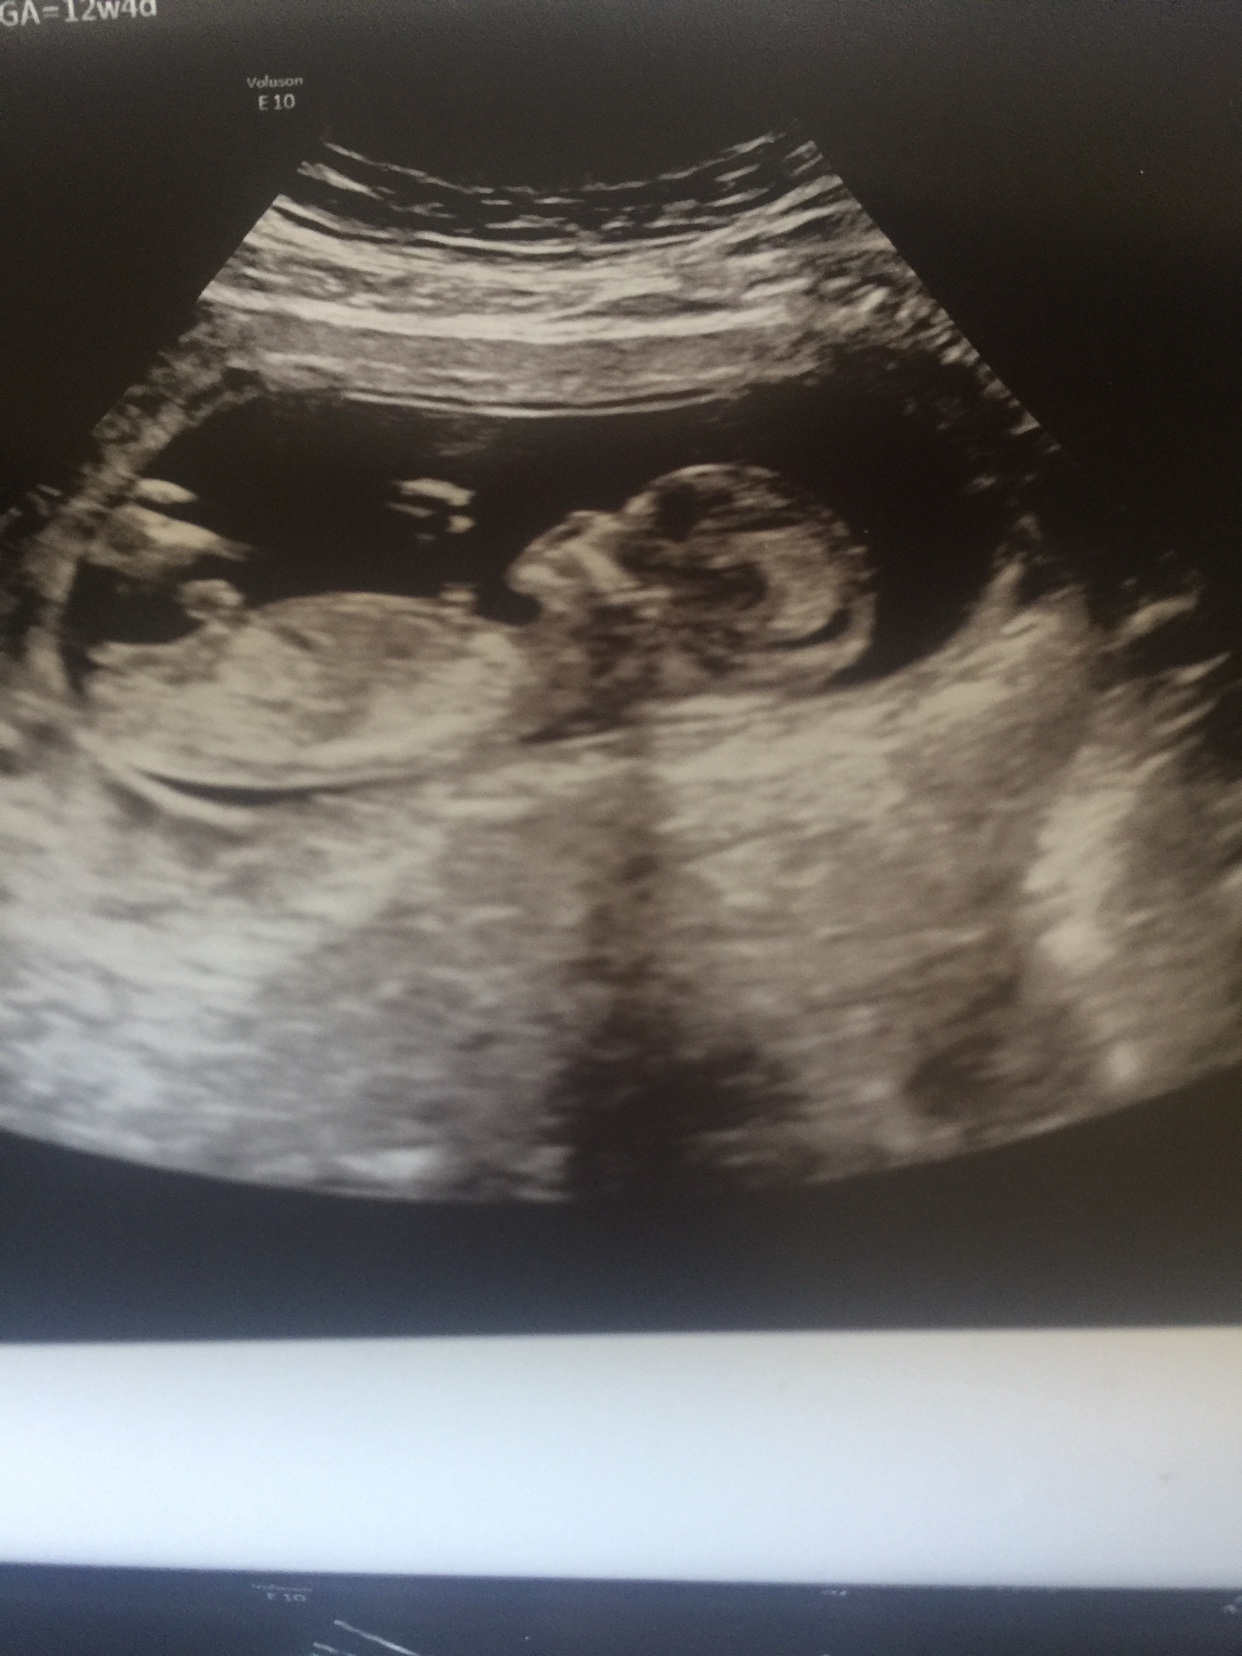

Gender guesses 12w4d ultrasound based on nub theory or skill theory Attachment 37379 Attachment 37380Attachment 37381